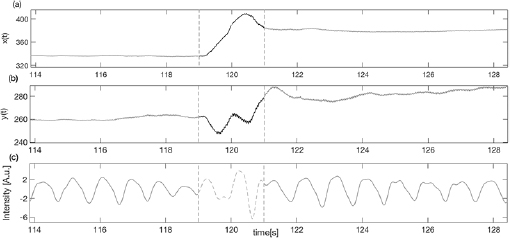

Hz,  Hz, and f p is the highest peak assumed to be the pulse frequency (measured in Hz). The signal with the highest SNR was selected as the target vPPG signal. Subsequently, the motion artefacts were automatically detected using the X–Y coordinates of facial movement (as shown in figure 1). Within a sliding window 1 s long, the first derivatives of X and Y coordinates (defined as

Hz, and f p is the highest peak assumed to be the pulse frequency (measured in Hz). The signal with the highest SNR was selected as the target vPPG signal. Subsequently, the motion artefacts were automatically detected using the X–Y coordinates of facial movement (as shown in figure 1). Within a sliding window 1 s long, the first derivatives of X and Y coordinates (defined as  and

and  ) were calculated. If the mean of

) were calculated. If the mean of  or

or  calculated inside the interval time was higher than a threshold (manually selected as 14 pixels s−1), the corresponding vPPG segment was labeled as artefactual and discarded from further analysis (see figure 2). Less than

calculated inside the interval time was higher than a threshold (manually selected as 14 pixels s−1), the corresponding vPPG segment was labeled as artefactual and discarded from further analysis (see figure 2). Less than  of the total number of segments were excluded from the successive procedure.

of the total number of segments were excluded from the successive procedure.

Figure 1. Tracking of the face according to horizontal (X axis) and vertical (Y axis) movement.

Standard image High-resolution imageFigure 2. Example of artefact movement removal on vPPG signal (c) using the X–Y tracking signals (a) and (b) as references of noise.